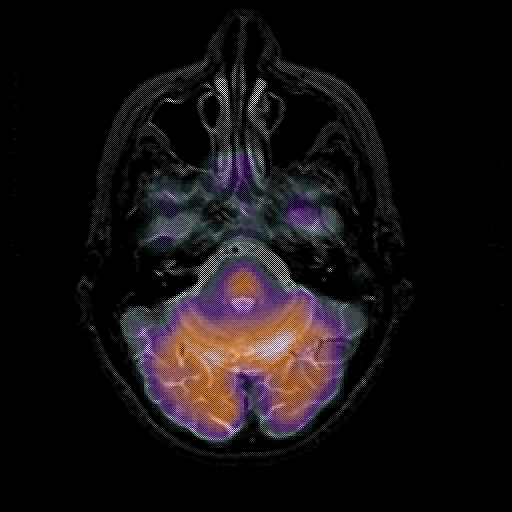

overlay 1: Slice 15

Slice 15

MRCBFCBF with

T1PDT2T1PDT2